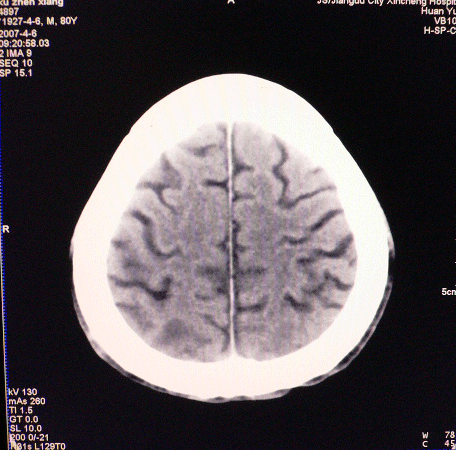

以下是引用狙击手在2007-4-8 22:45:00的发言:[br]出血?从患者的症状考虑病灶应该在左侧大脑半球的基底节区或颞顶部,如此小的病灶引起上述症状的可能性不大,患者可能有梗塞(时间短,目前ct还看不见)或是tia发作,再者像这样的线条形出血的确不多见,但还是有可能的,曾经碰到有外伤类似出血,复查后消失,所以还是慎重一点,短期复查即可。

以下是引用dyqct在2007-4-8 16:25:00的发言:[br]支持左侧放射冠区少量出血。